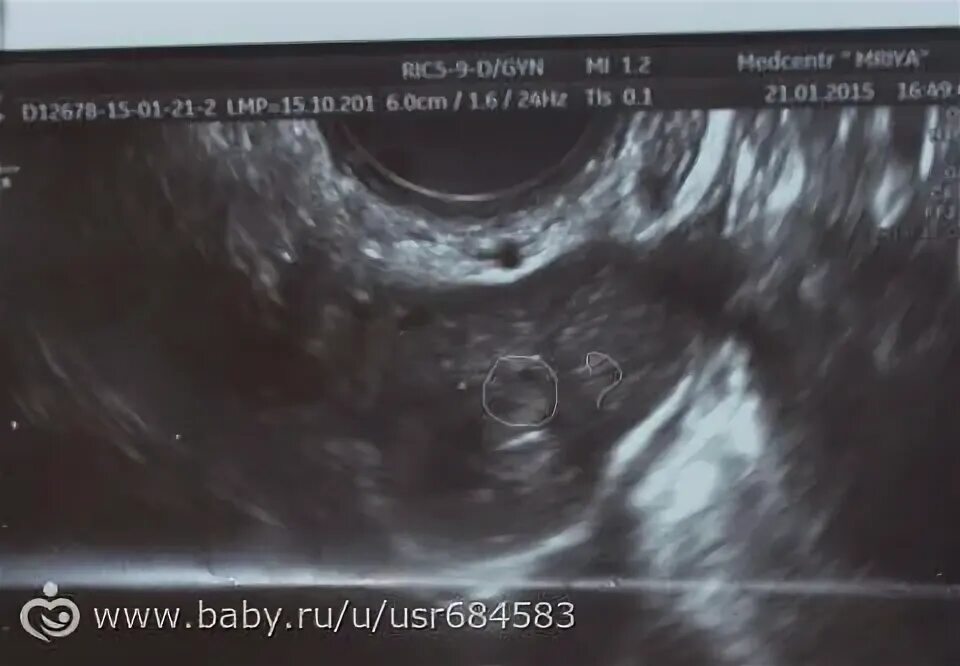

Тест положительный узи не видит